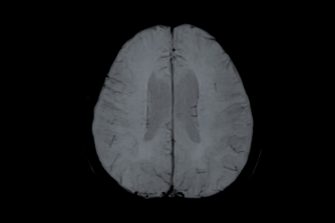

In this latest study, recently published in the journal Human Brain Mapping, Dr Haeme Park and Associate Professor Justine Gatt, who hold joint positions at UNSW Psychology and NeuRA, looked at how both emotion and cognition are influenced by the environment and genetics, using functional MRI (fMRI) scans on twins.

While the participants were completing the tasks, the fMRI machine was scanning their brain to measure its activity.

Processing the fMRI scans show you which part of the brain light up for different processes, and how strongly the brain is activated can be measured on a scale.